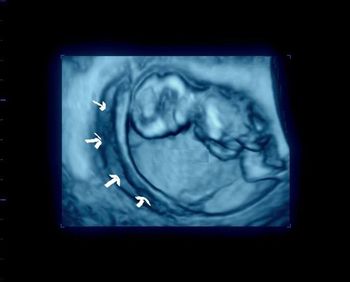

What is your diagnosis based on these images from a 35-week fetus?